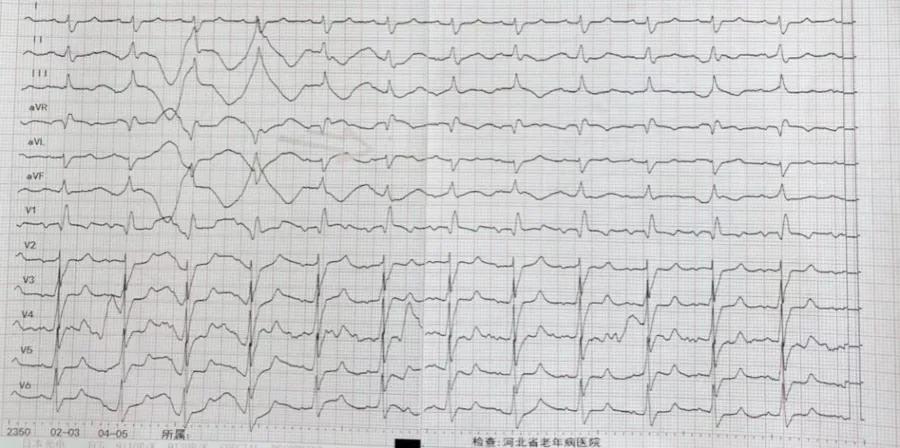

入院时查心电图

经体外反搏治疗后